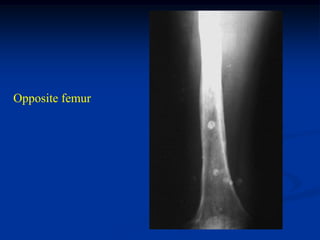

Opposite femur